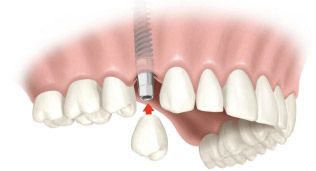

Восстановление зуба на имплантате

Протезирование - установка коронки на имплантат

Финальный этап восстановления зубного ряда, крепление коронковой части зуба к вросшему в костную ткань титановому основанию - имплантату.